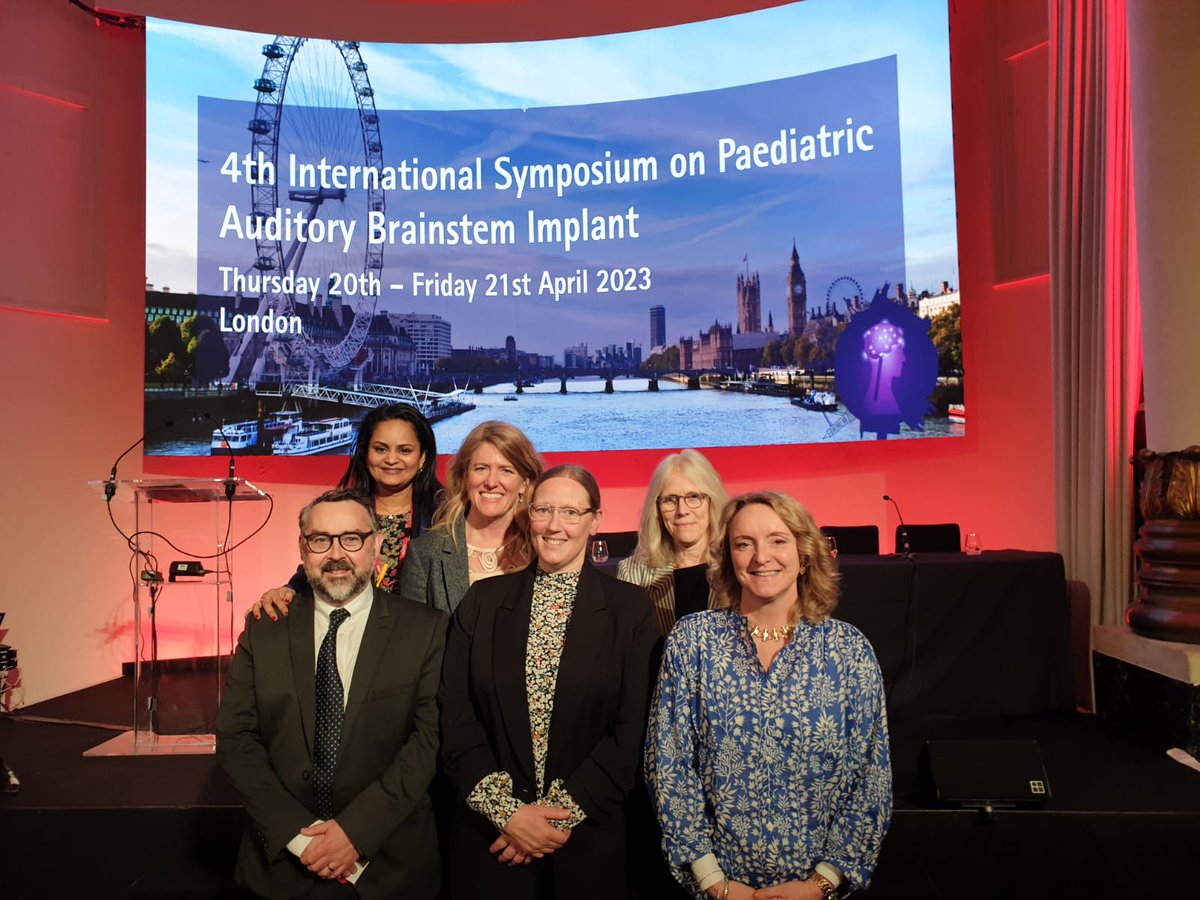

"4th International Symposium on Paediatric Auditory Brainstem Implant (ABI)" is coming tomorrow! Check it out. ( eventbrite.co.uk/e/4th-internat… Eventbrite